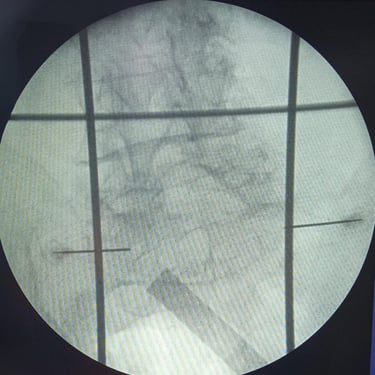

Fractura Lumbar Osteoporótica / Vertebroplastía y Bloqueo Lumbar Selectivo

La fractura lumbar osteoporótica y la artrosis lumbar son causas frecuentes de dolor crónico y limitación funcional en el adulto mayor. La osteoporosis debilita las vértebras, favoreciendo fracturas incluso ante esfuerzos mínimos, mientras que la artrosis genera desgaste articular e inflamación. La vertebroplastía percutánea permite estabilizar las vértebras fracturadas mediante la inyección de cemento óseo, proporcionando alivio rápido y mejorando la movilidad. En casos de dolor persistente por artrosis, el bloqueo lumbar selectivo ayuda a reducir la inflamación y el dolor. Ambas técnicas son procedimientos mínimamente invasivos que mejoran la calidad de vida y facilitan la recuperación funcional.